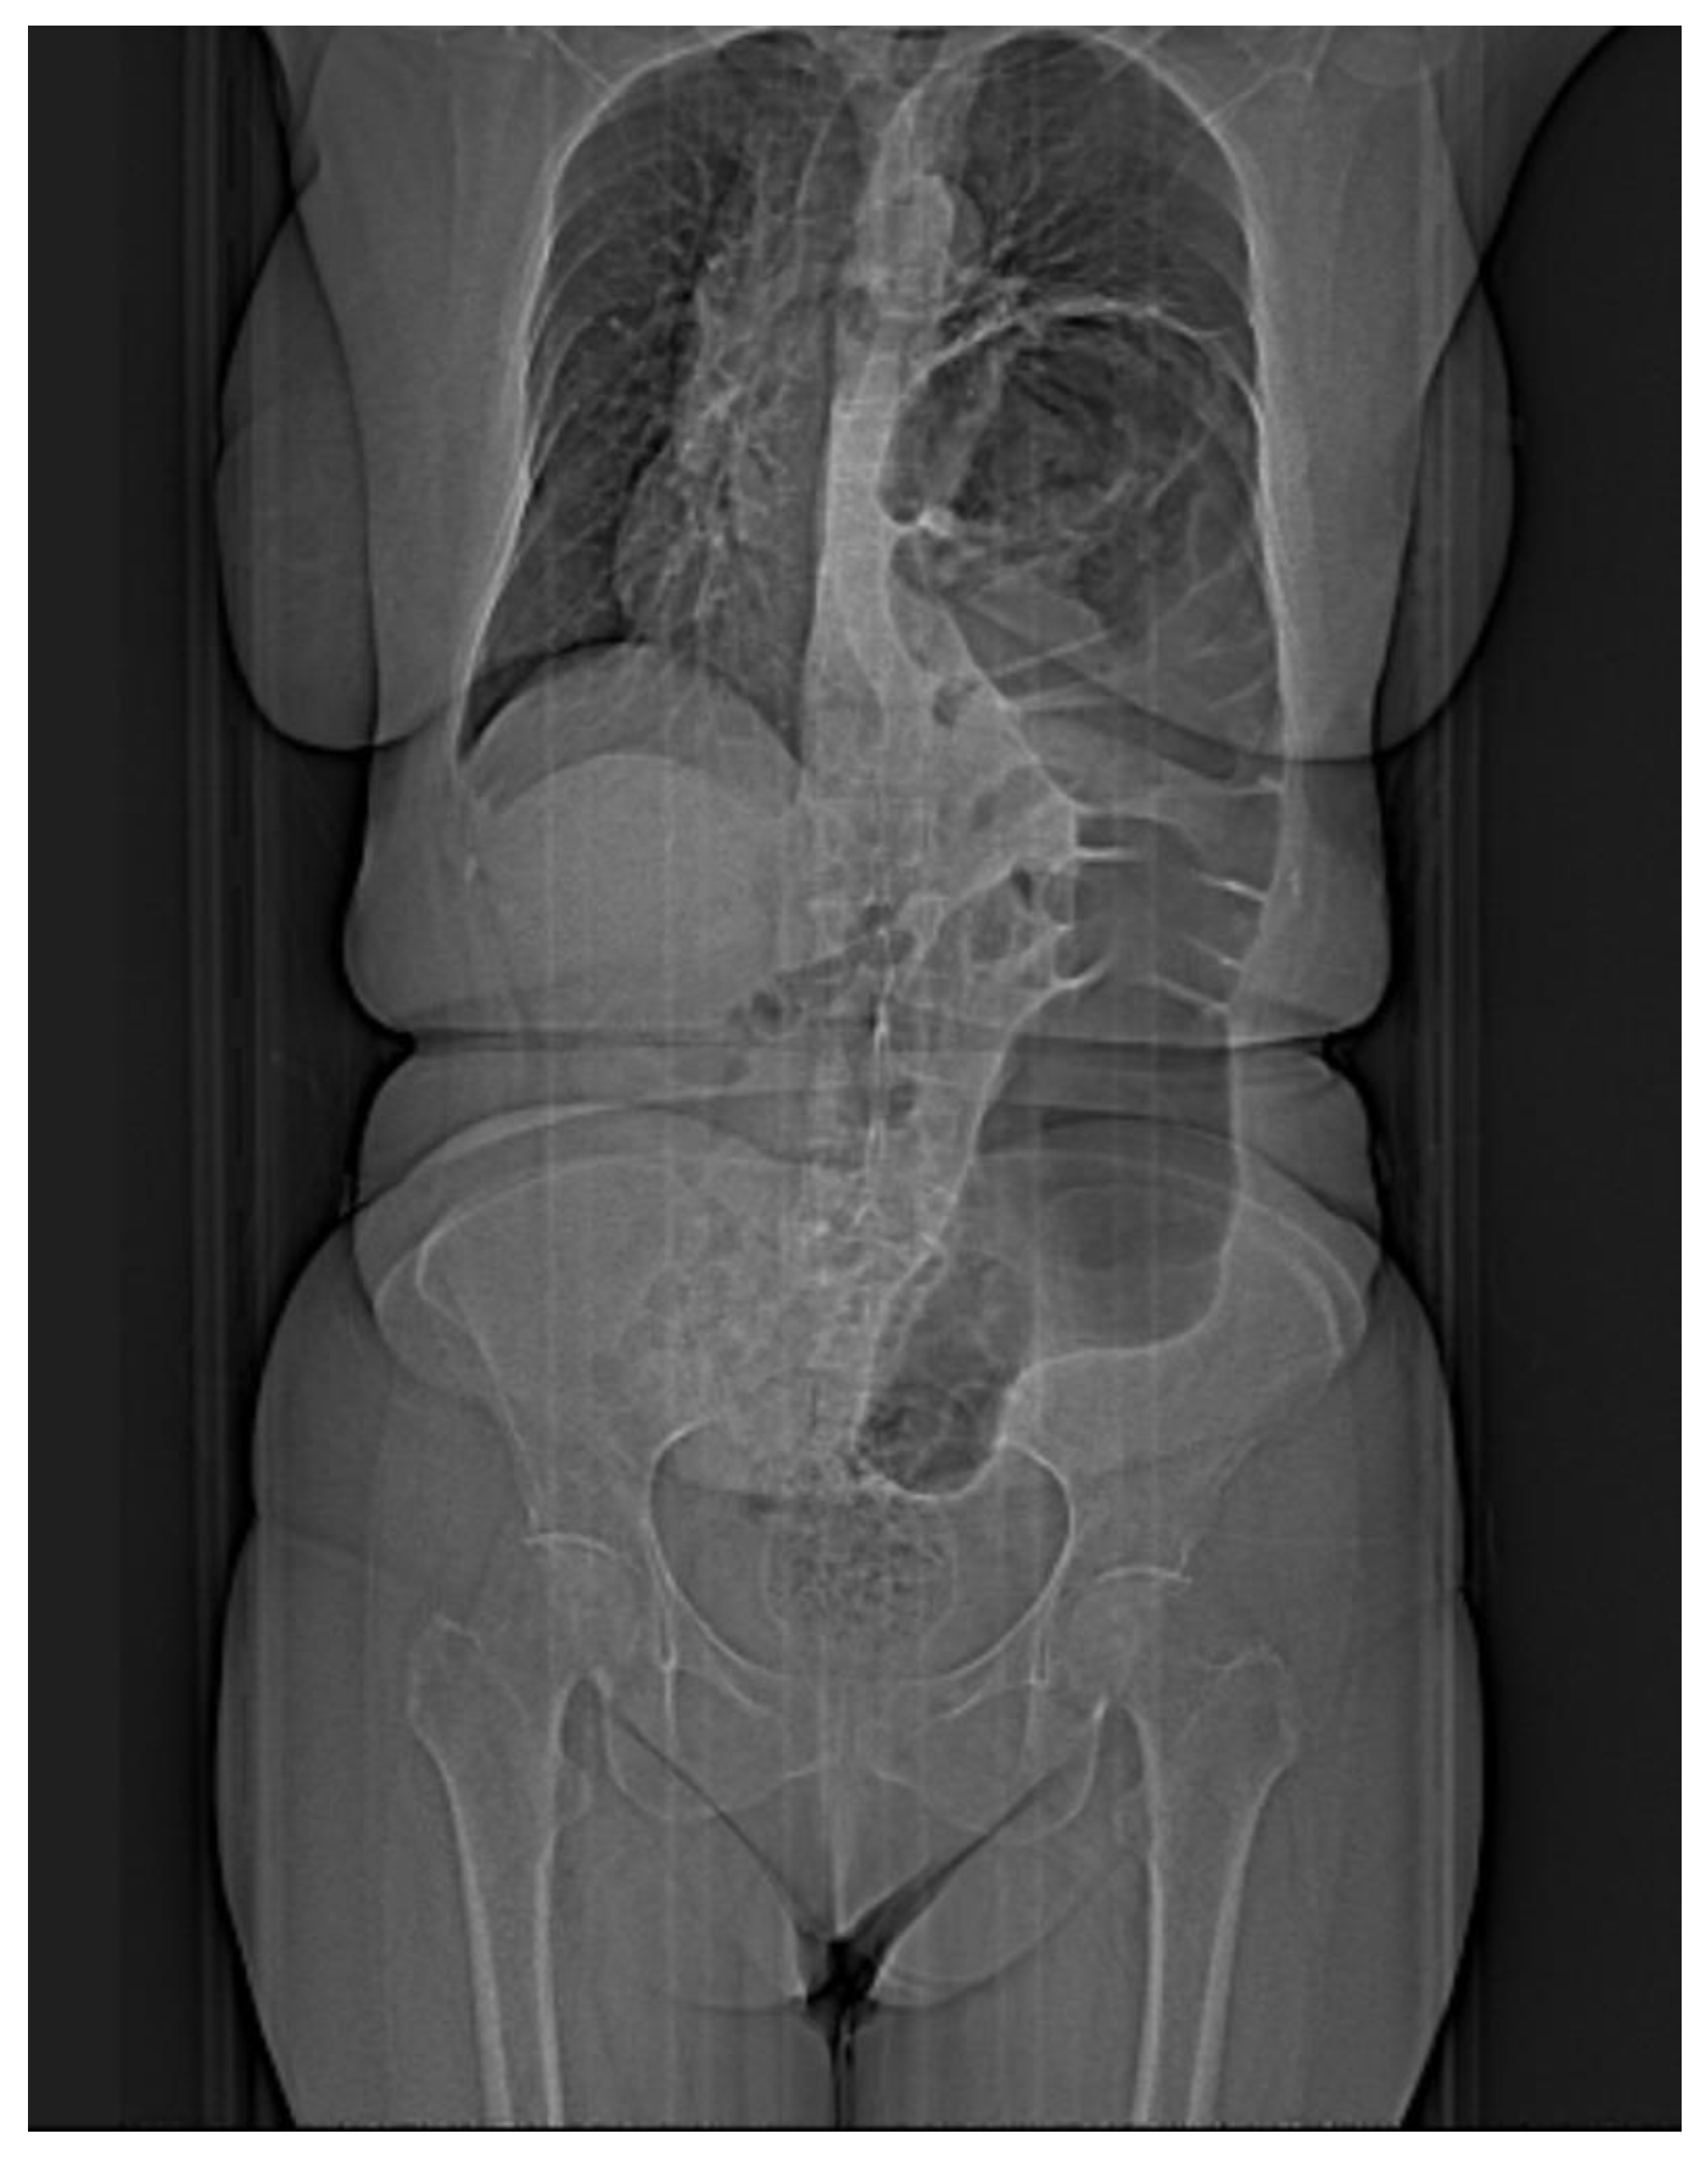

Chest X-ray is most often the first radiological investigation performed in these patients (90%). Chest and abdominal X-ray is recommended to be performed in multiple incidences, including the Trendelenburg position. Specific radiological signs are opacification of the lung bases, especially of the posterior fields depending on the contents of the hernial sac (Figure 1), intrathoracic localization of the abdominal viscera, and left hemidiaphragm elevation (more than 4 cm) with or without atelectasis. In general, diagnosis is more difficult when the hernial orifice is located on the right hemidiaphragm.

Figure 1. Simple imaging assessment—radiography. The presence of the colon, ascended transdiaphragmatically through a Bochdalek hernia, at the level of the left hemithorax is noted.